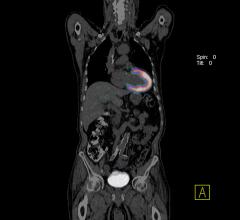

July 14, 2016 — Adding F-18-choline positron emission tomography (PET) to multi-parametric prostate magnetic resonance ...